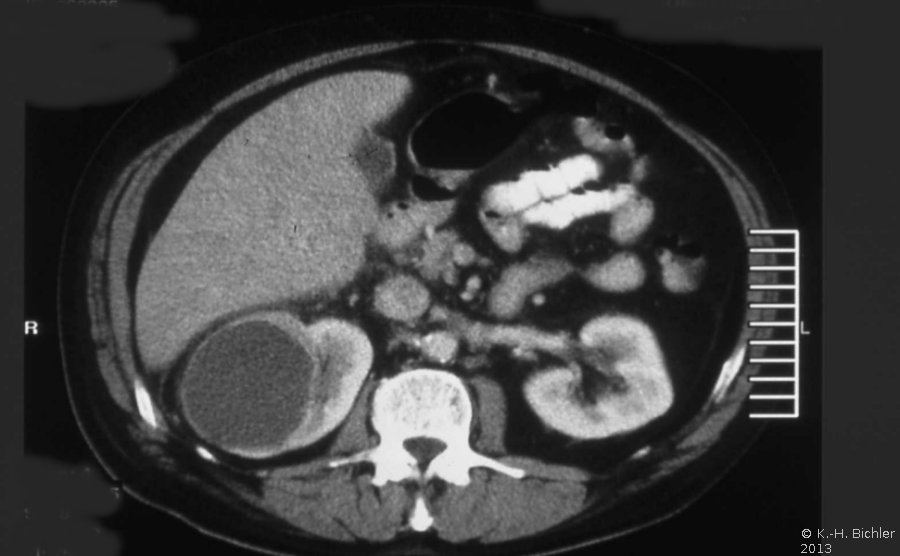

Diagnose und Behandlung von komplexen renalen Zysten bzw. unklaren Befunden umfassen eine Kombination von Sonographie, Urographie und CT (Abbildung 1). Dadurch soll eine Abgrenzung zwischen gutartigen und bösartigen Veränderungen erfolgen.